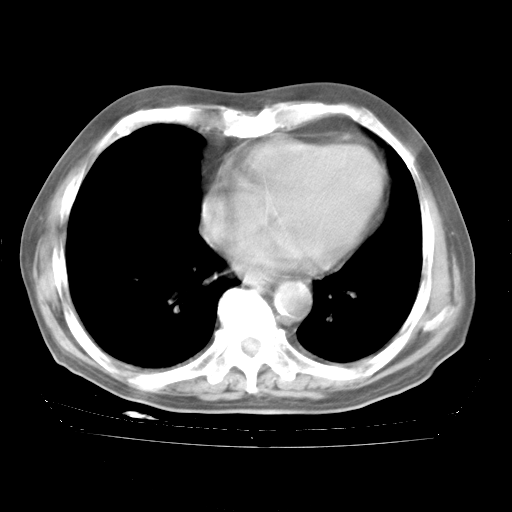

4月28日肺部CT——再次出现类似去年5月9日——透光度降低,“间质性”改变。

4月28日肺部CT——再次出现类似去年5月9日——磨玻璃样、间有“粟粒样”改变。

4月28日肺部CT

个人阅读4.14日肺部CT平扫:纵隔窗无异常,但肺窗示:双下肺内、后基底段有片絮状侵润影,部位以后基底段为著,以间质改变为主,呈急性肺泡炎征像,和首次住院影像学有相似之处。仅是个人读片,明日请相关专家再读片哈。其它建议同上。

1、108#的是4月14日的胸部CT(发此贴时还没看着28日的CT)。14日的胸部CT其实已经出现改变(如108#所述),个人认为28日的胸部CT除纵膈窗疑似有双侧胸膜增厚或少量胸积液(可行胸部B超明确)外,与4月14日对照病变有所加重;2、已经给予“异烟肼、利福平、乙胺丁醇”抗痨治疗?如果是,甲强龙80mg可缓慢减量;如果环磷酰胺已停用,暂不使用;3、中性粒细胞92%,明显升高,目前体温情况?注意合并细菌感染可能,使用左氧氟沙星情况下,是否联用B-内酰胺类抗菌药物?另外是查免疫全套非风湿全套。

今请临免主任会诊后认为:4月14日胸部CT已有双下肺间质性改变。患者病情复发多系激素减量过快不正规所致。目前甲强龙80mg/日,一周后酌情开始减量,不易过快。环磷酰胺若已停用,暂不使用。他同意目前抗菌药物使用,但应考虑是否加用B-内酰胺类抗菌药物(中性细胞明显增高);2、结核复发目前依据不足;3、若免疫全套各项指标正常,考虑多系特发性肺间质炎可能大。4、加强支持,并注意保护胃黏膜。